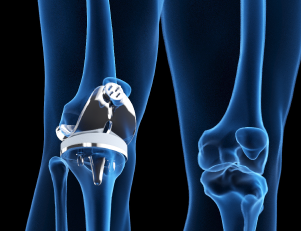

Prothèses osseuses : quand les bactéries vous empêchent de marcher

Conférence de Fany Reffuveille (BIOS, URCA), déc. 2022